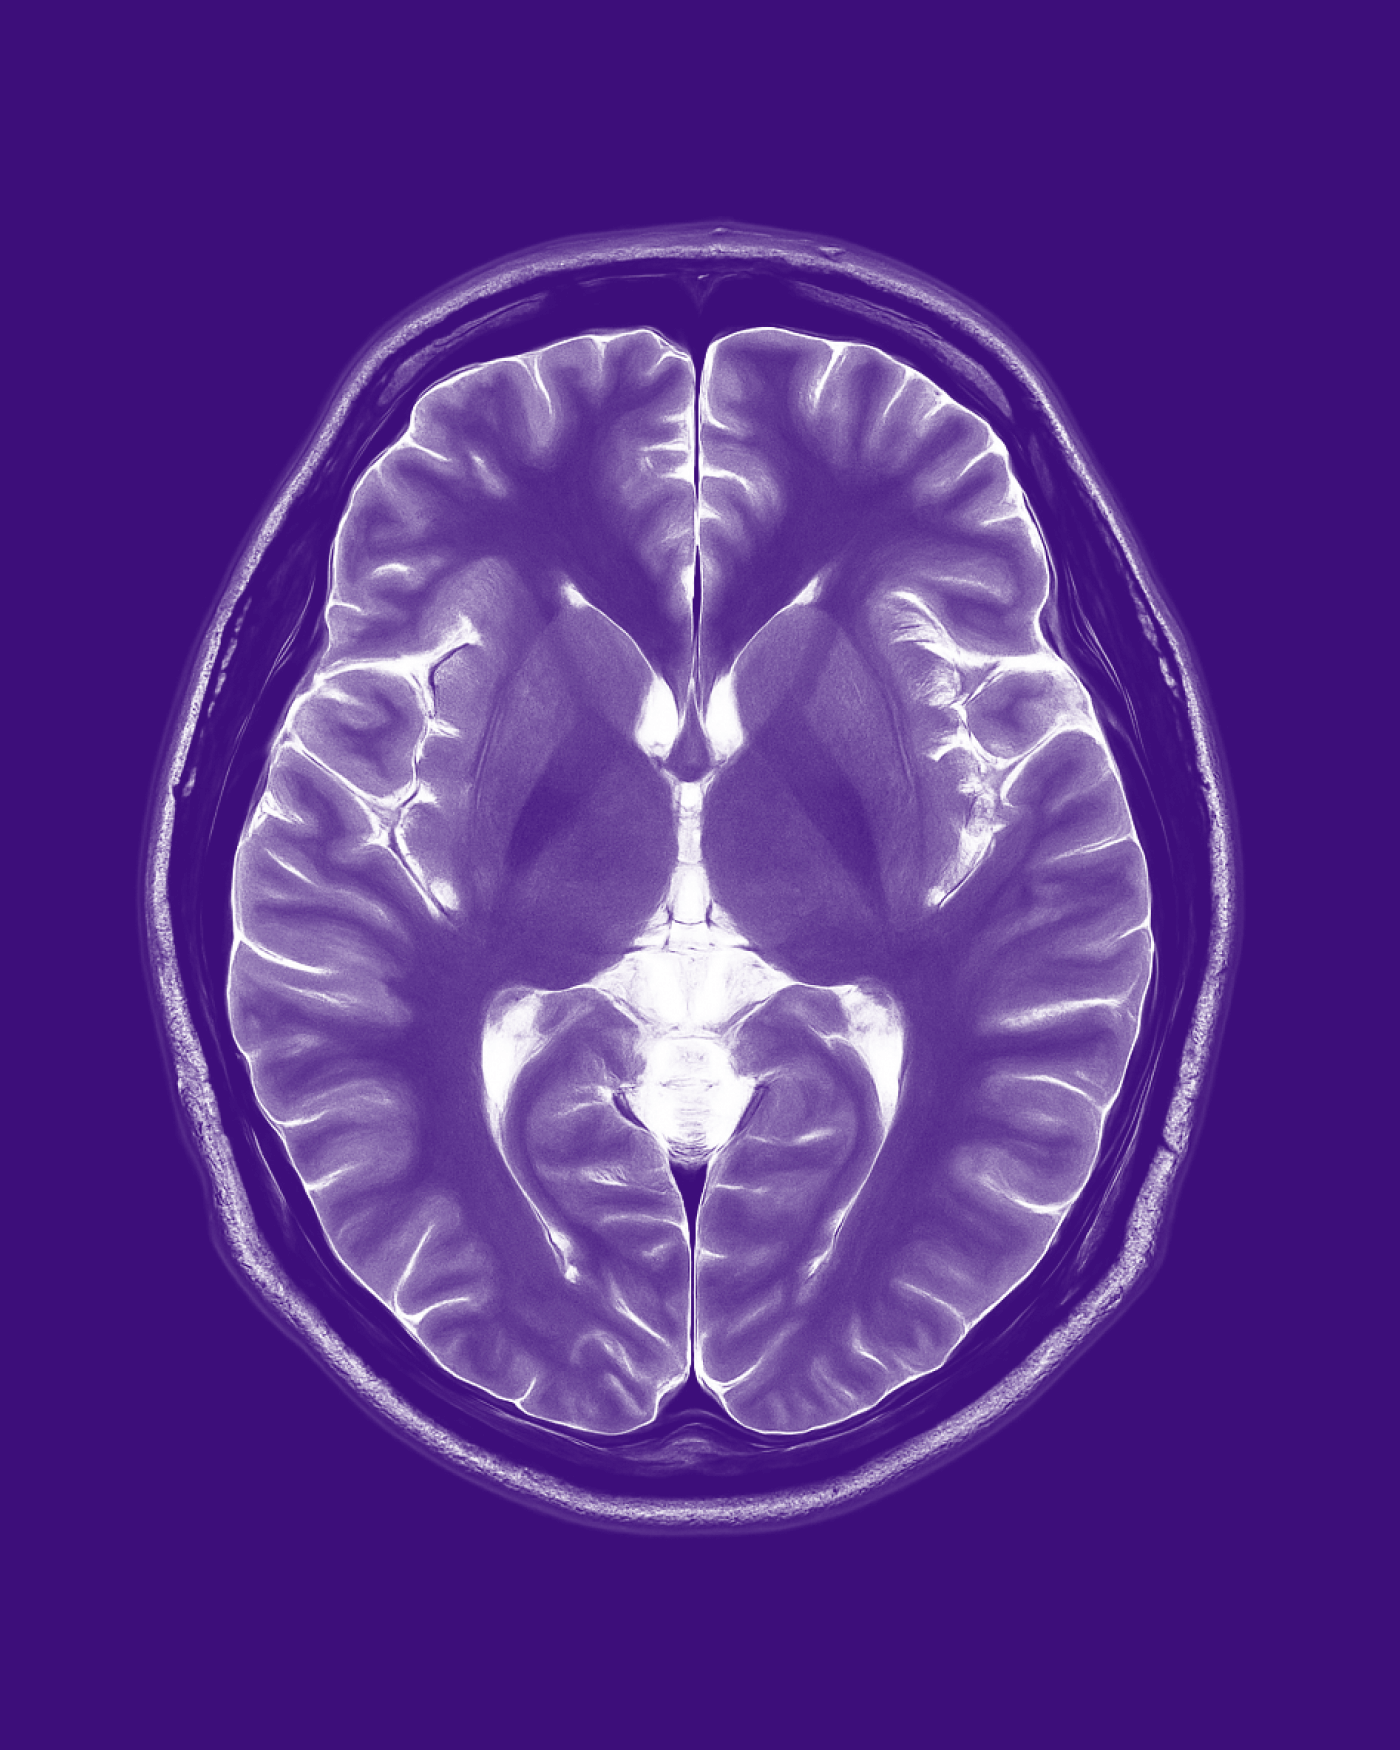

Commonly used by women seeking a long-term, reversible contraceptive method, Depo-Provera is highly effective, with a success rate of over 99% when used correctly. However, it is associated with various known side effects, such as weight gain, mood changes, decreased bone density, and menstrual irregularities. Based upon research published in March 2024, users of Depo-Provera face a 5.6 times greater chance of developing meningiomas, a form of brain tumor, than those who do not use Depo-Provera. Despite this, the makers of Depo-Provera do not warn women about this risk.